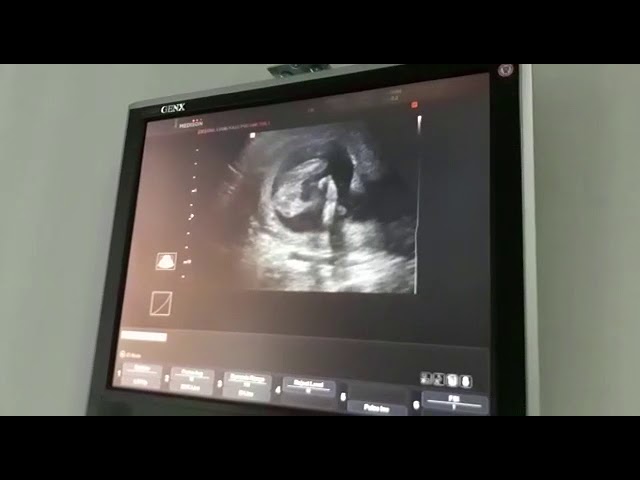

В данном видео можно увидеть ребенка на 17 неделе: